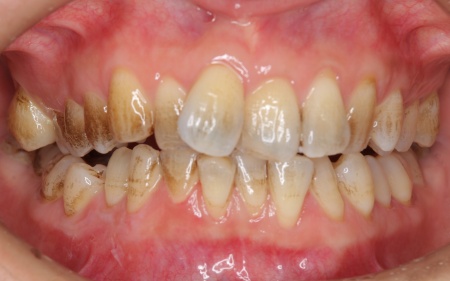

30代女性 デコボコした歯並びをワイヤー矯正とセラミック治療で改善した症例

拝見したところ、歯が全体的にずれたりねじれたりして生えており、歯並びがデコボコしていました。 また、数本の歯にはプラスチックの詰め物が装着されていましたが、経年的な劣化により歯との間に段差が生じています。これも噛み合わせのバランスを崩す原因のひとつになっていると考えられました。 歯並びや噛み合わせの乱れをこのまま放置すると、歯磨きがしにくくなり虫歯や歯周病のリスクが高まるほか、特定の歯に強い力がかかり続けることで将来的に歯の寿命に影響を及ぼすおそれもあります。

治療前